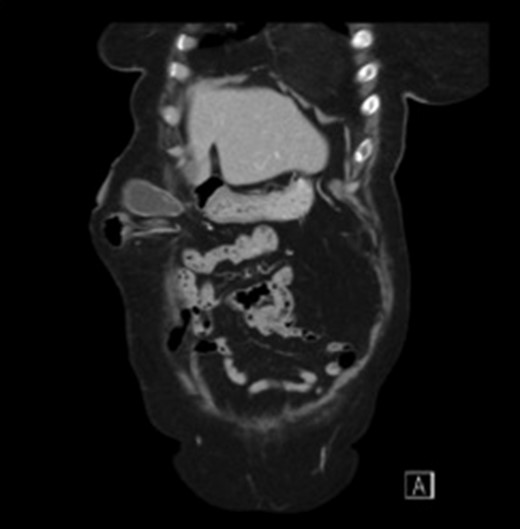

Subsequent Computed Tomography (CT) of the abdomen and pelvis revealed a parastomal hernia containing the gallbladder (Figs 1 and 2). There was no evidence of cholecysitis or choledocholithiasis. CBD was dilated to 9 mm without any filling defects.

Axial view CT scan of the gallbladder in the parastomal hernia.